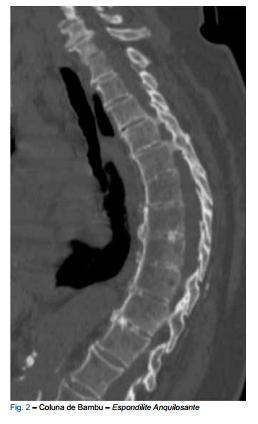

“Computed tomography (CT) scans of the spine are among the most frequently performed neuroradiologic exams, studying several pathologies namely ...